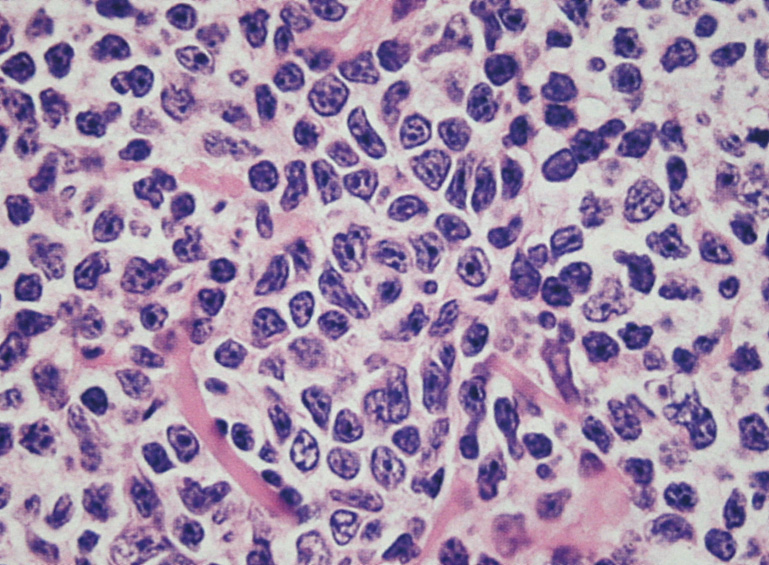

- 典型例はmarginal zoneのcentrocyte-like cellの増殖といわれるが非典型例も多い

- 分化してplasma cell様の形態をとる. Dutcher body(核内偽封入体)など異型所見あり。

| centrocyte-like cell | monocytoid cell | plasmacytoid |